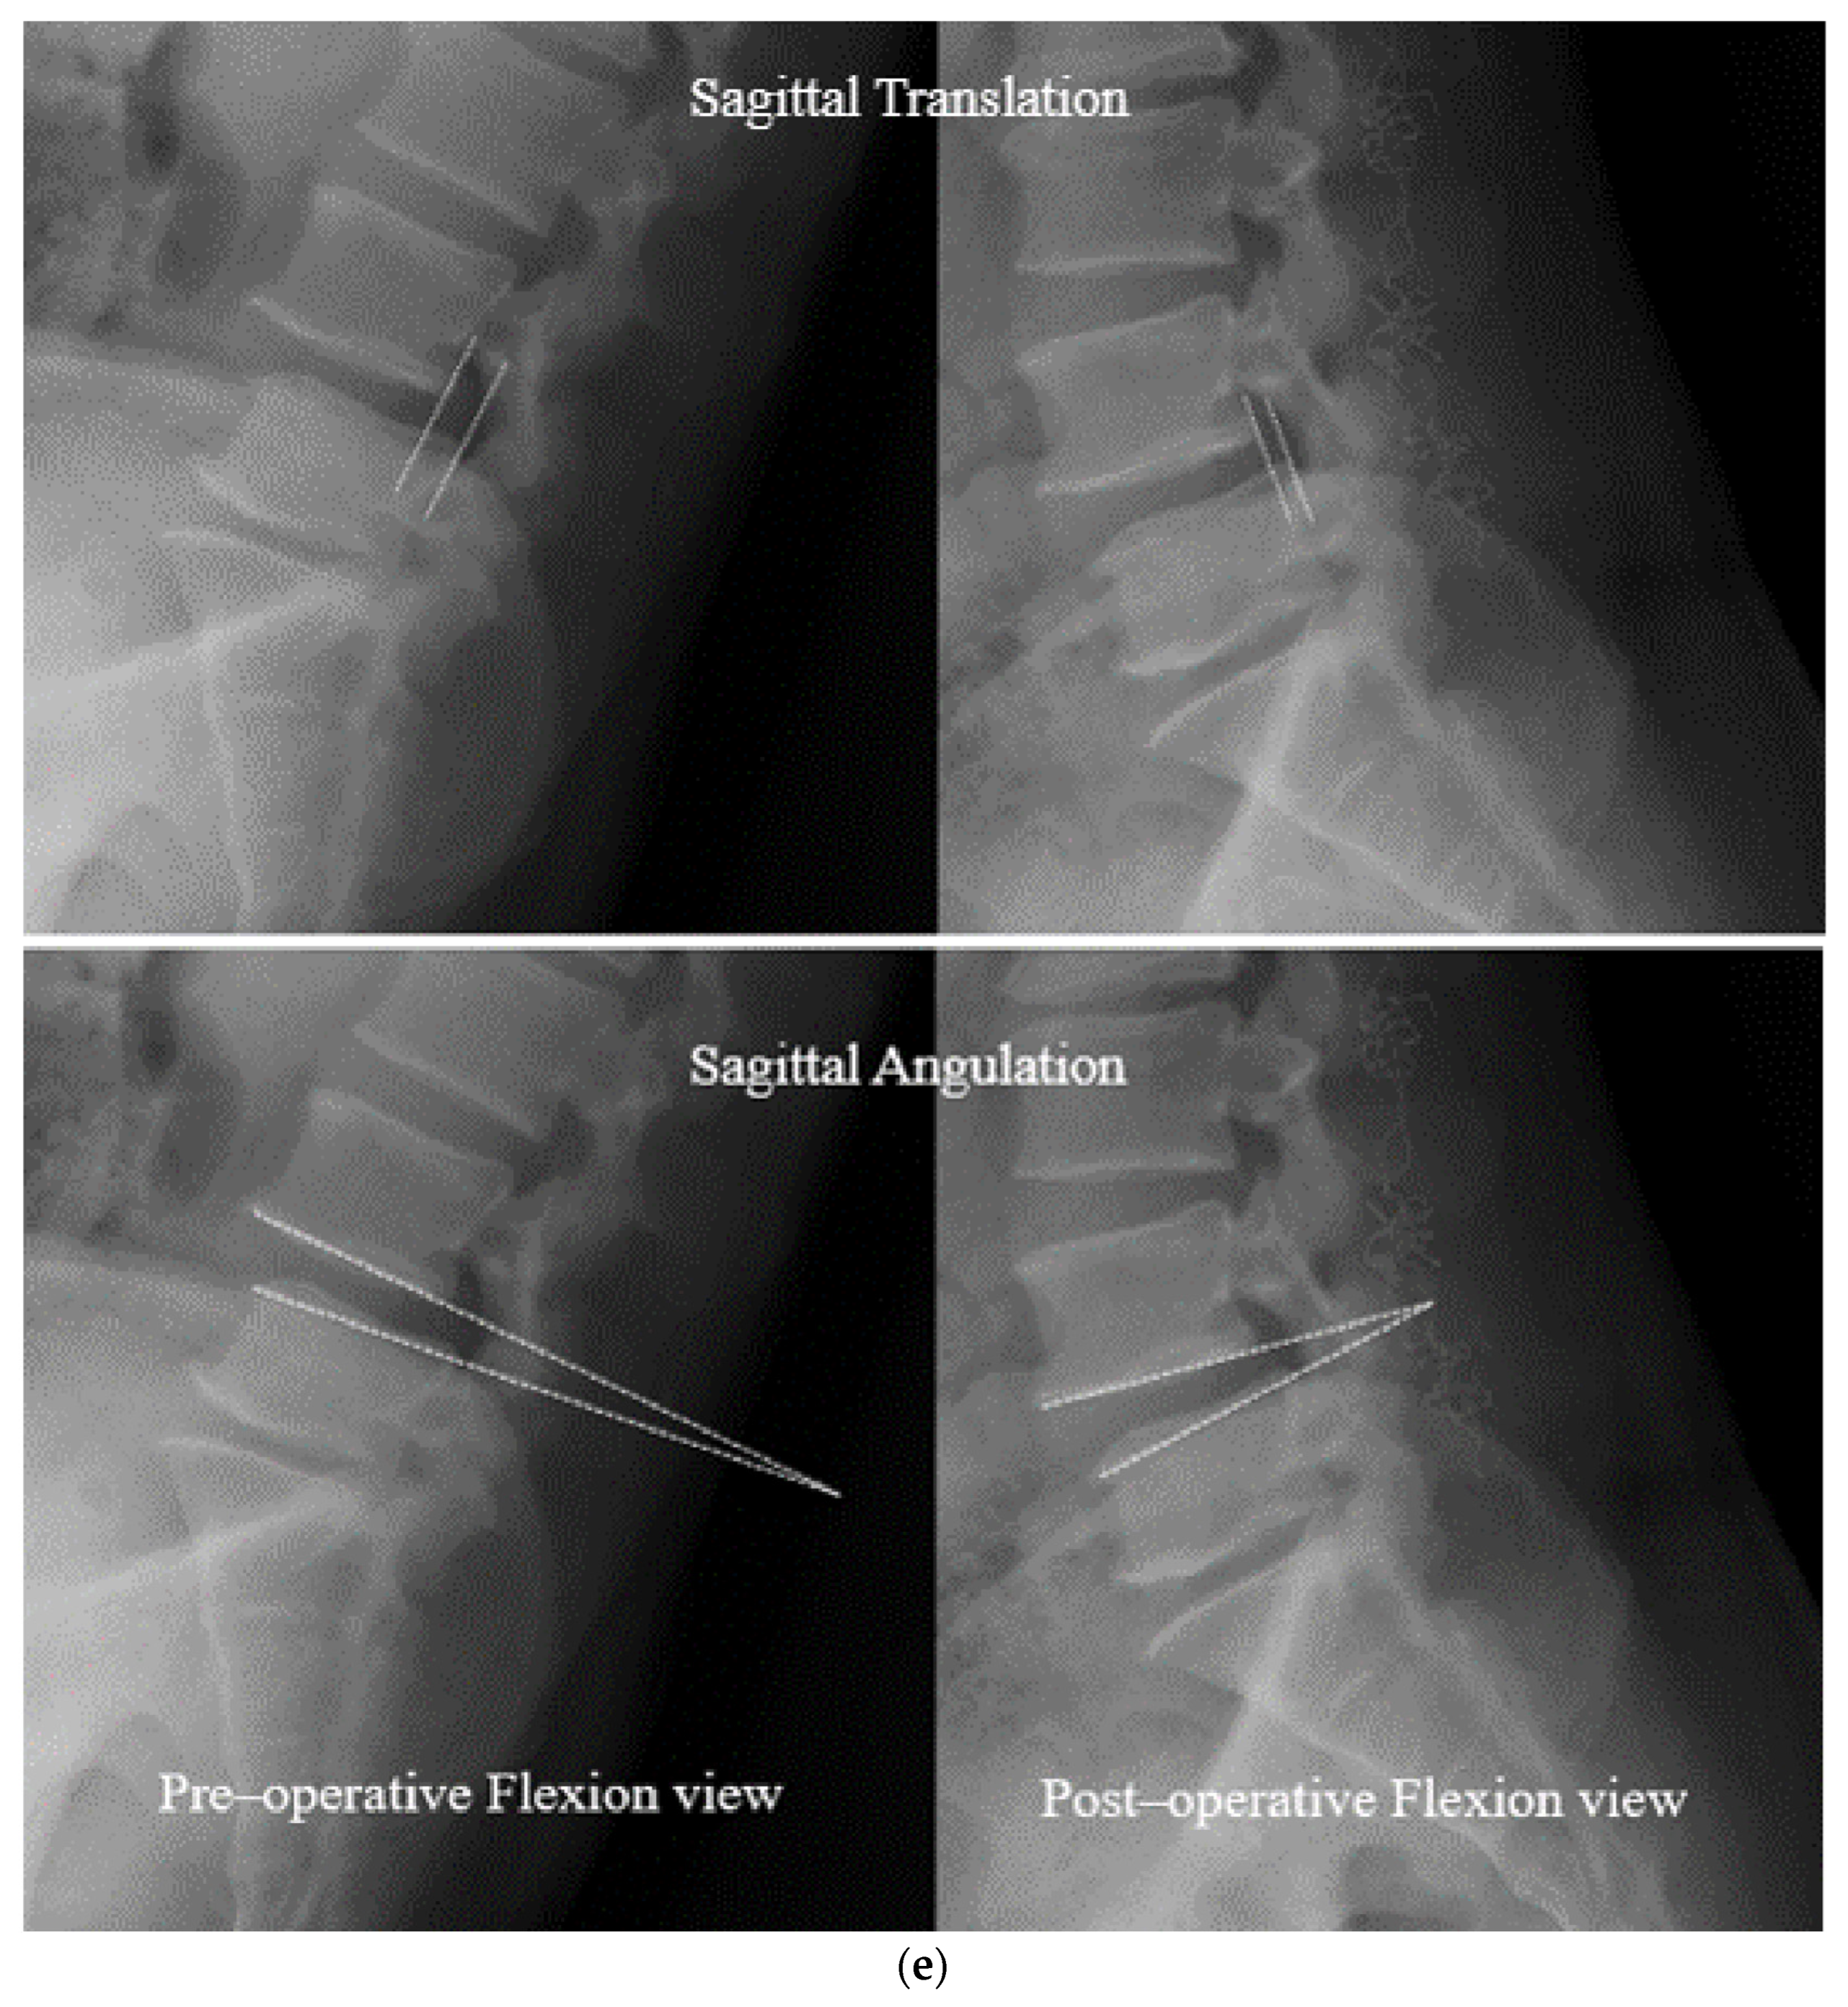

- Open Midline Decompression

- Ligament Reconstruction